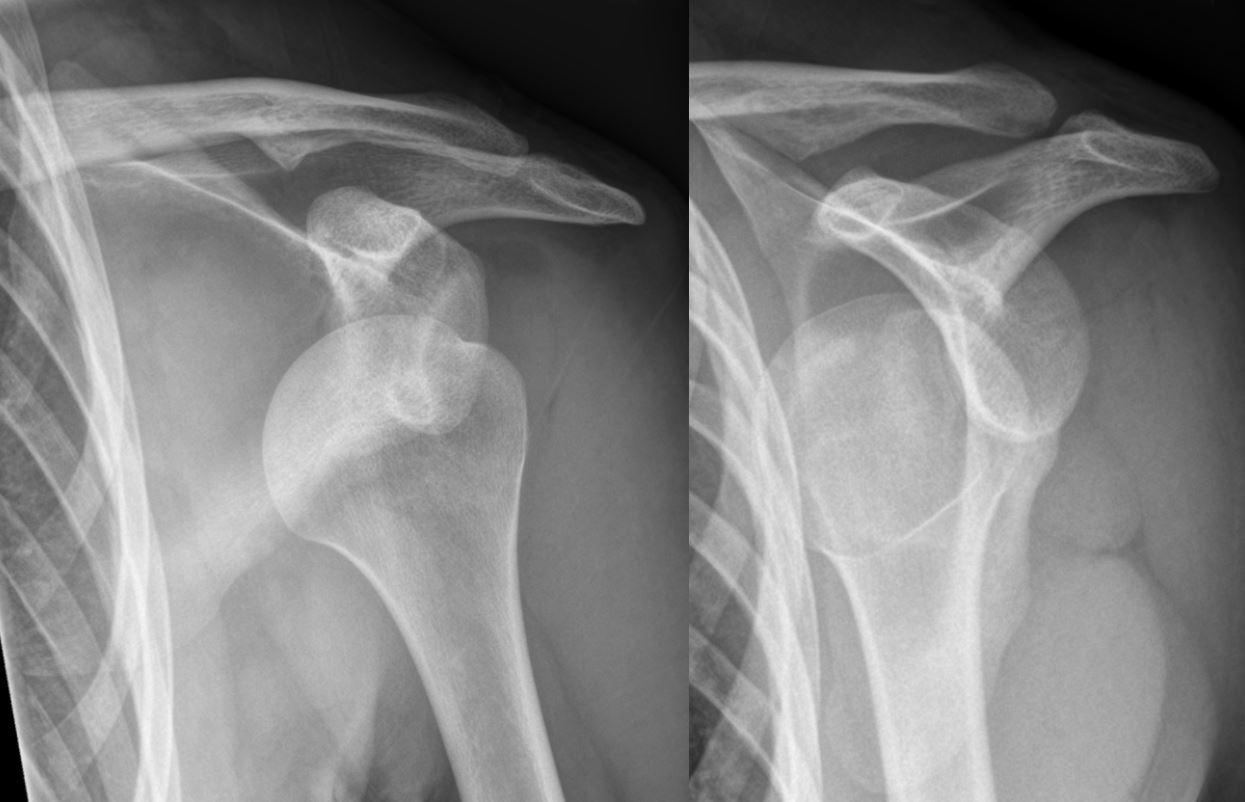

The human body contains 206 bones that are held together by connective tissues such as ligaments and tendons. Over half of the bones in the body are contained in the hands and feet. Bones meet or are joined at a joint and there are hundreds of joints in the human body, some moveable and some immovable. From a fighting perspective we are primarily interested in the major joints that can be dislocated through the destruction of the joint complex with a tearing of the connective tissues that hold the bones of the joint in place. Using the shoulder as an example, the shoulder is the most mobile joint in the body, and it is held in place by the rotator cuff tendons. Techniques that serve to dislocate the shoulder joint will frequently cause a full or partial tear in the rotator cuff tendons and a dislocation of the shoulder joint.

Learning to dislocate a joint and to destroy the joint complex requires basic knowledge of the anatomy and physiology of joints and the limits of their normal range of motion. Anatomy and physiology of joints should be a routine part of the education of a martial artist. In addition to learning about joint anatomy and physiology martial artists need to know the kinesiology (science of body movement) or range of motion of a joint because the destruction of a joint will be accomplished by moving the joint beyond its normal range of motion. One example, again using the shoulder, is to move the shoulder joint into extreme hyperextension which will separate the head of the humerus from the glenoid fossa tearing the rotator cuff tendons and the ligaments of the joint capsule.

The following images demonstrate techniques to dislocate the shoulder joint tearing the rotator cuff tendons and the ligaments of the joint capsule. The first photograph shows a standing arm lock to shoulder dislocation, while the second technique employs a “Guillotine choke” with the radial bone applied to the attacker’s airway and positioned to crush the airway. The next step is the dislocation of the shoulder joint. Many of the major bony landmarks of your body can be used as natural surfaces over which to bend and destroy an attacker’s joints. Learn how to use them effectively.

X-ray of dislocated shoulder Source: Hellerhoff / CC BY-SA (https://creativecommons.org/licenses/by-sa/3.0)